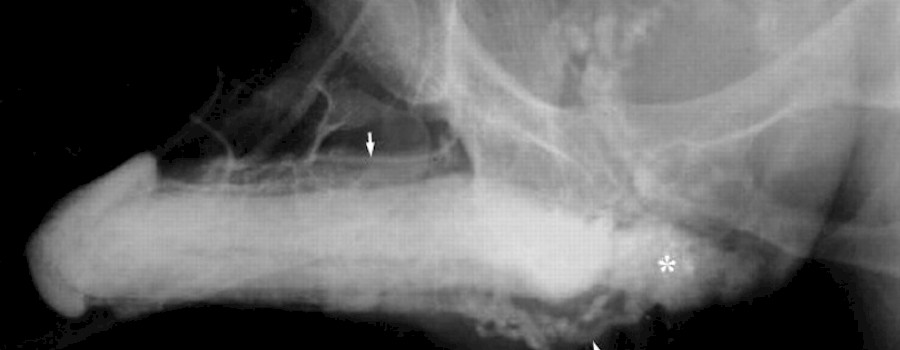

Röntgen trotz Schwangerschaft

Wird eine schwangere Frau einer Bestrahlung ausgesetzt, dann kann es bei dem ungeborenen Kind zu Fehlbildungen und Entwicklungsstörungen kommen. Zudem besteht für das Kind ein erhöhtes Risiko, an Krebs oder Leukämie zu erkranken.